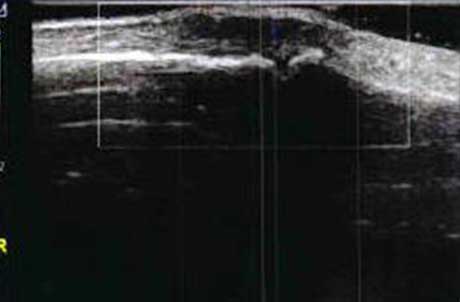

1、动态观察滑膜血流信号,早期监测RA活动

肌骨超声血流成像可清晰反映滑膜的血流情况,观测滑膜周边及内部异常血流信号的增多、血管翳增生程度,以及呈现出点状、星点状或枝状的不同形态,做到在RA的早期发现异常图像变化。通过对图像中血流信号的多少及区域范围进行评分,以此来辅助判断RA的活动程度。

Ⅰ级血流

滑膜内异常血流信号:少量点状血流信号

Ⅱ级血流

滑膜内异常血流信号:较多点状,短线状血流信号

Ⅲ级血流

滑膜内异常血流信号:丰富的网状及树状血流信号